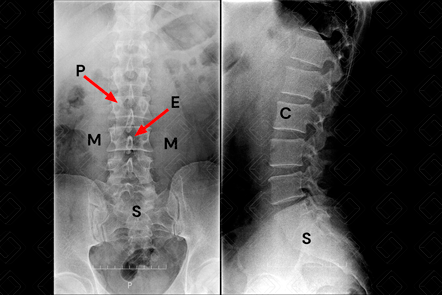

Legenda das siglas: C = corpos vertebrais; E = processo espinhoso; M = músculo psoas; P = pedículos; S = sacro [cms-watermark] .

Radiografia em AP: A coluna lombar inteira deve ser visualizada, incluindo a borda inferior de D12 e parte do sacro. Faz parte do protocolo básico.

Radiografia em perfil: Também faz parte do protocolo básico de avaliação. Adequada avaliação da porção posterior dos corpos vertebrais e pedículos. Excelente incidência para avaliação de fraturas.